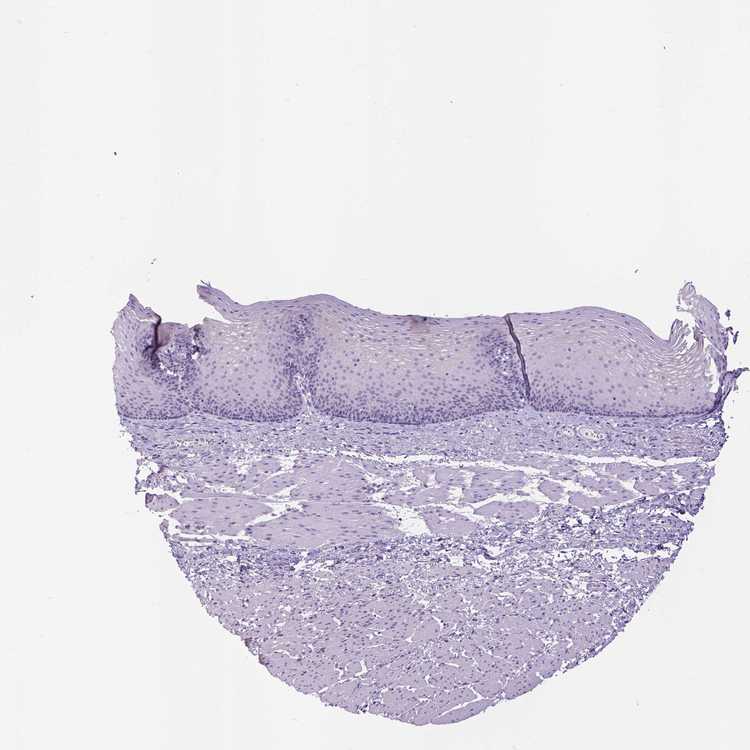

ESOPHAGUS - Antibody stainingi

Antibody staining in the annotated cell types in the current human tissue is reported as not detected, low, medium, or high, based on conventional immunohistochemistry profiling in selected tissues. This score is based on the combination of the staining intensity and fraction of stained cells.

Each image is clickable and will lead to virtual microscopy that enables deeper exploration of all samples and also displays staining intensity scores, fraction scores and subcellular localization as well as patient and tissue information for each sample.

Antibody HPA052397

Squamous epithelial cells Not detected